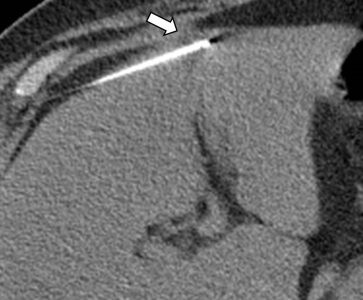

Η διαδερμική βιοψία είναι μια ελάχιστα επεμβατική μέθοδος λήψης υλικού από τον όγκο για κυτταρολογική και ιστολογική εξέταση από εστιακές αλλοιώσεις του ήπατος, του πνεύμονα, του μαστού, του νεφρού κλπ. Συνιστάται από τον κλινικό ιατρό ανάλογα με το είδος και το μέγεθος της βλάβης και πραγματοποιείται με ασφάλεια από επεμβατικό ακτινολόγο συνήθως με την καθοδήγηση αξονικού τομογράφου ή υπερήχων. Στη σύγχρονη ογκολογική θεραπεία, όπου γίνεται προσπάθεια καταπολέμησης του καρκίνου σε μοριακό επίπεδο, κρίνεται αναγκαία η ακριβής ιστολογική ταυτοποίηση του όγκου, ώστε να εφαρμοσθεί εξατομικευμένη θεραπεία για το βέλτιστο αποτέλεσμα.

Διαδερμικά κατευθυνόμενη βιοψία αδενοκαρκινώματος πνεύμονα